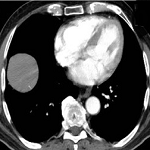

Discovery of a giant pulmonary hydatid cyst on thoracic deformation in a child

Hind Cherrabi, Mohamed Amine Oukhouya

PAMJ. 2022; 42: 39. Published 16 May 2022